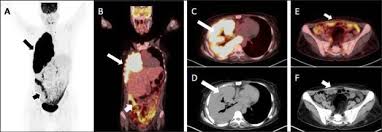

Pet Ct In The Diagnosis Of Localized Malignant Pleural Mesothelioma Clinical Imaging

Pet Ct In The Diagnosis Of Localized Malignant Pleural Mesothelioma Clinical Imaging from els-jbs-prod-cdn.jbs.elsevierhealth.com

Early detection of the fatal and incurable mesothelioma and the later provision of radiation, surgical and palliative asbestosis treatments are known to help a patient to have the best possible chance to extend and enhance the quality of life remaining. Provide pertinent illustrative figures of pet/ct and ct for malignant pleural mesothelioma. This retrospective study aimed to investigate the prognostic value of the suvmax in patients with mpm. European journal of nuclear medicine and molecular imaging, 2014. pet/ct scan problem of pleural effusion therapy for mesothelioma sufferers early detection of the deadly and incurable. He underwent vats with pleural drainage, biopsy and extensive decortication. These imaging tests will show visual evidence of mesothelioma. Pathology revealed epithelioid type malignant mesothelioma involving parietal and visceral pleura with clear margins (stage pt1bn0).

European journal of nuclear medicine and molecular imaging, 2014. Given the presence of the mesothelium in different parts of the body, mesothelioma can arise in various locations 17:. At left is a ct scan, while the center image is a pet scan. Sensitivity, specificity and accuracy were respectively 86, 89 and 87%; The tumor originates from cells of the visceral or parietal pleural and is linked to asbestos exposure with a median latency of 44.6 years .due to the latency between exposure and onset of mesothelioma and the ongoing use of asbestos in parts of the world, the incidence is expected to rise. Current perspectives maria bonomi,1 costantino de filippis,2 egesta lopci,3 letizia gianoncelli,1 giovanna rizzardi,4 eleonora cerchiaro,1 luigi bortolotti,4 alessandro zanello,2 giovanni luca ceresoli1 1department of oncology, thoracic and gu oncology unit, 2department of radiology, cliniche humanitas gavazzeni, bergamo, 3nuclear medicine. Kazuhiro kitajima, hidetoshi matsuo, atsushi kono, kozo kuribayashi, takashi kijima, masaki hashimoto, seiki hasegawa, takamichi murakami, koichiro yamakado. The qualitative assessment was statistically different (p=0.0020, χ). Have been diagnosed with mesothelioma, your doctor may use this test to see if the cancer has spread to lymph nodes or other parts of the body. pet scans are often paired with ct scans to provide doctors with the most accurate view of a patient's body: A tissue biopsy will finalize whether or not a patient has this cancer. It can help identify the best therapies to control the cancer while maximizing quality. When a ct scan is performed, patients may also undergo a pet scan.

191 all treatments were planned based on ct and pet/ct imaging. Given the presence of the mesothelium in different parts of the body, mesothelioma can arise in various locations 17:. pet/ct scan problem of pleural effusion therapy for mesothelioma sufferers early detection of the deadly and incurable. A pet scan is the best method to determine if mesothelioma has spread to other parts of the body. pet/ct did not show any abnormal fdg uptake in the right pleura or remainder of the chest.